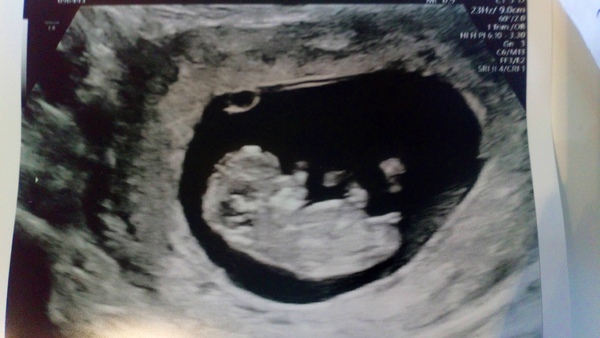

Everything was OK, measuring to dates and a very wriggly baby! Can't describe how relieved I am, 2 weeks to go til 12 week scan.

@monkerina thanks! Scan today was good! Saw and heard the little heartbeat. I'm dated at 7 weeks today which is a a couple days behind where I thought I was - but the professor didn't think it was an issue

I have a follow up scan in 2 weeks- so hope it continues To develop normally!

Also the professor told me 10 weeks is when I can stop worrying and start enjoying the pregnancy because the risk is pretty much eliminated by then! So fx for you!!!